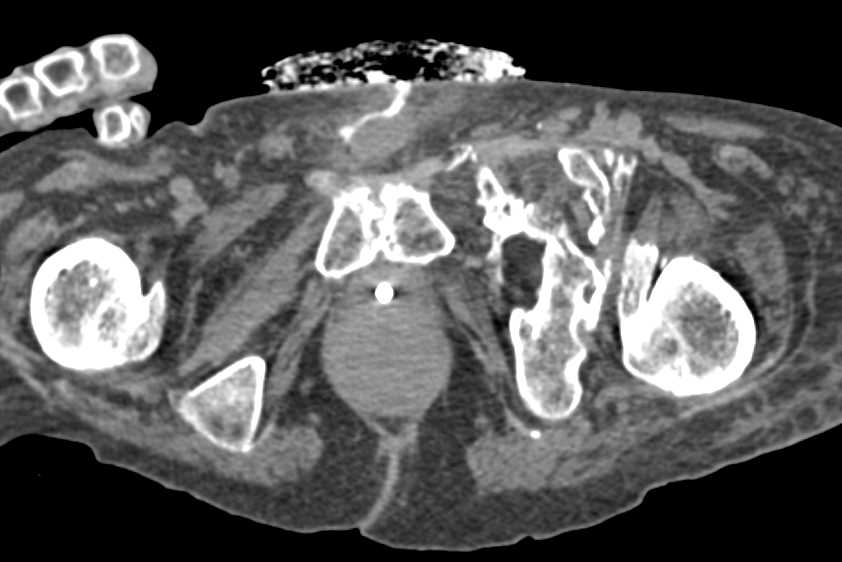

Liver Metastases from a Carcinoid Tumor